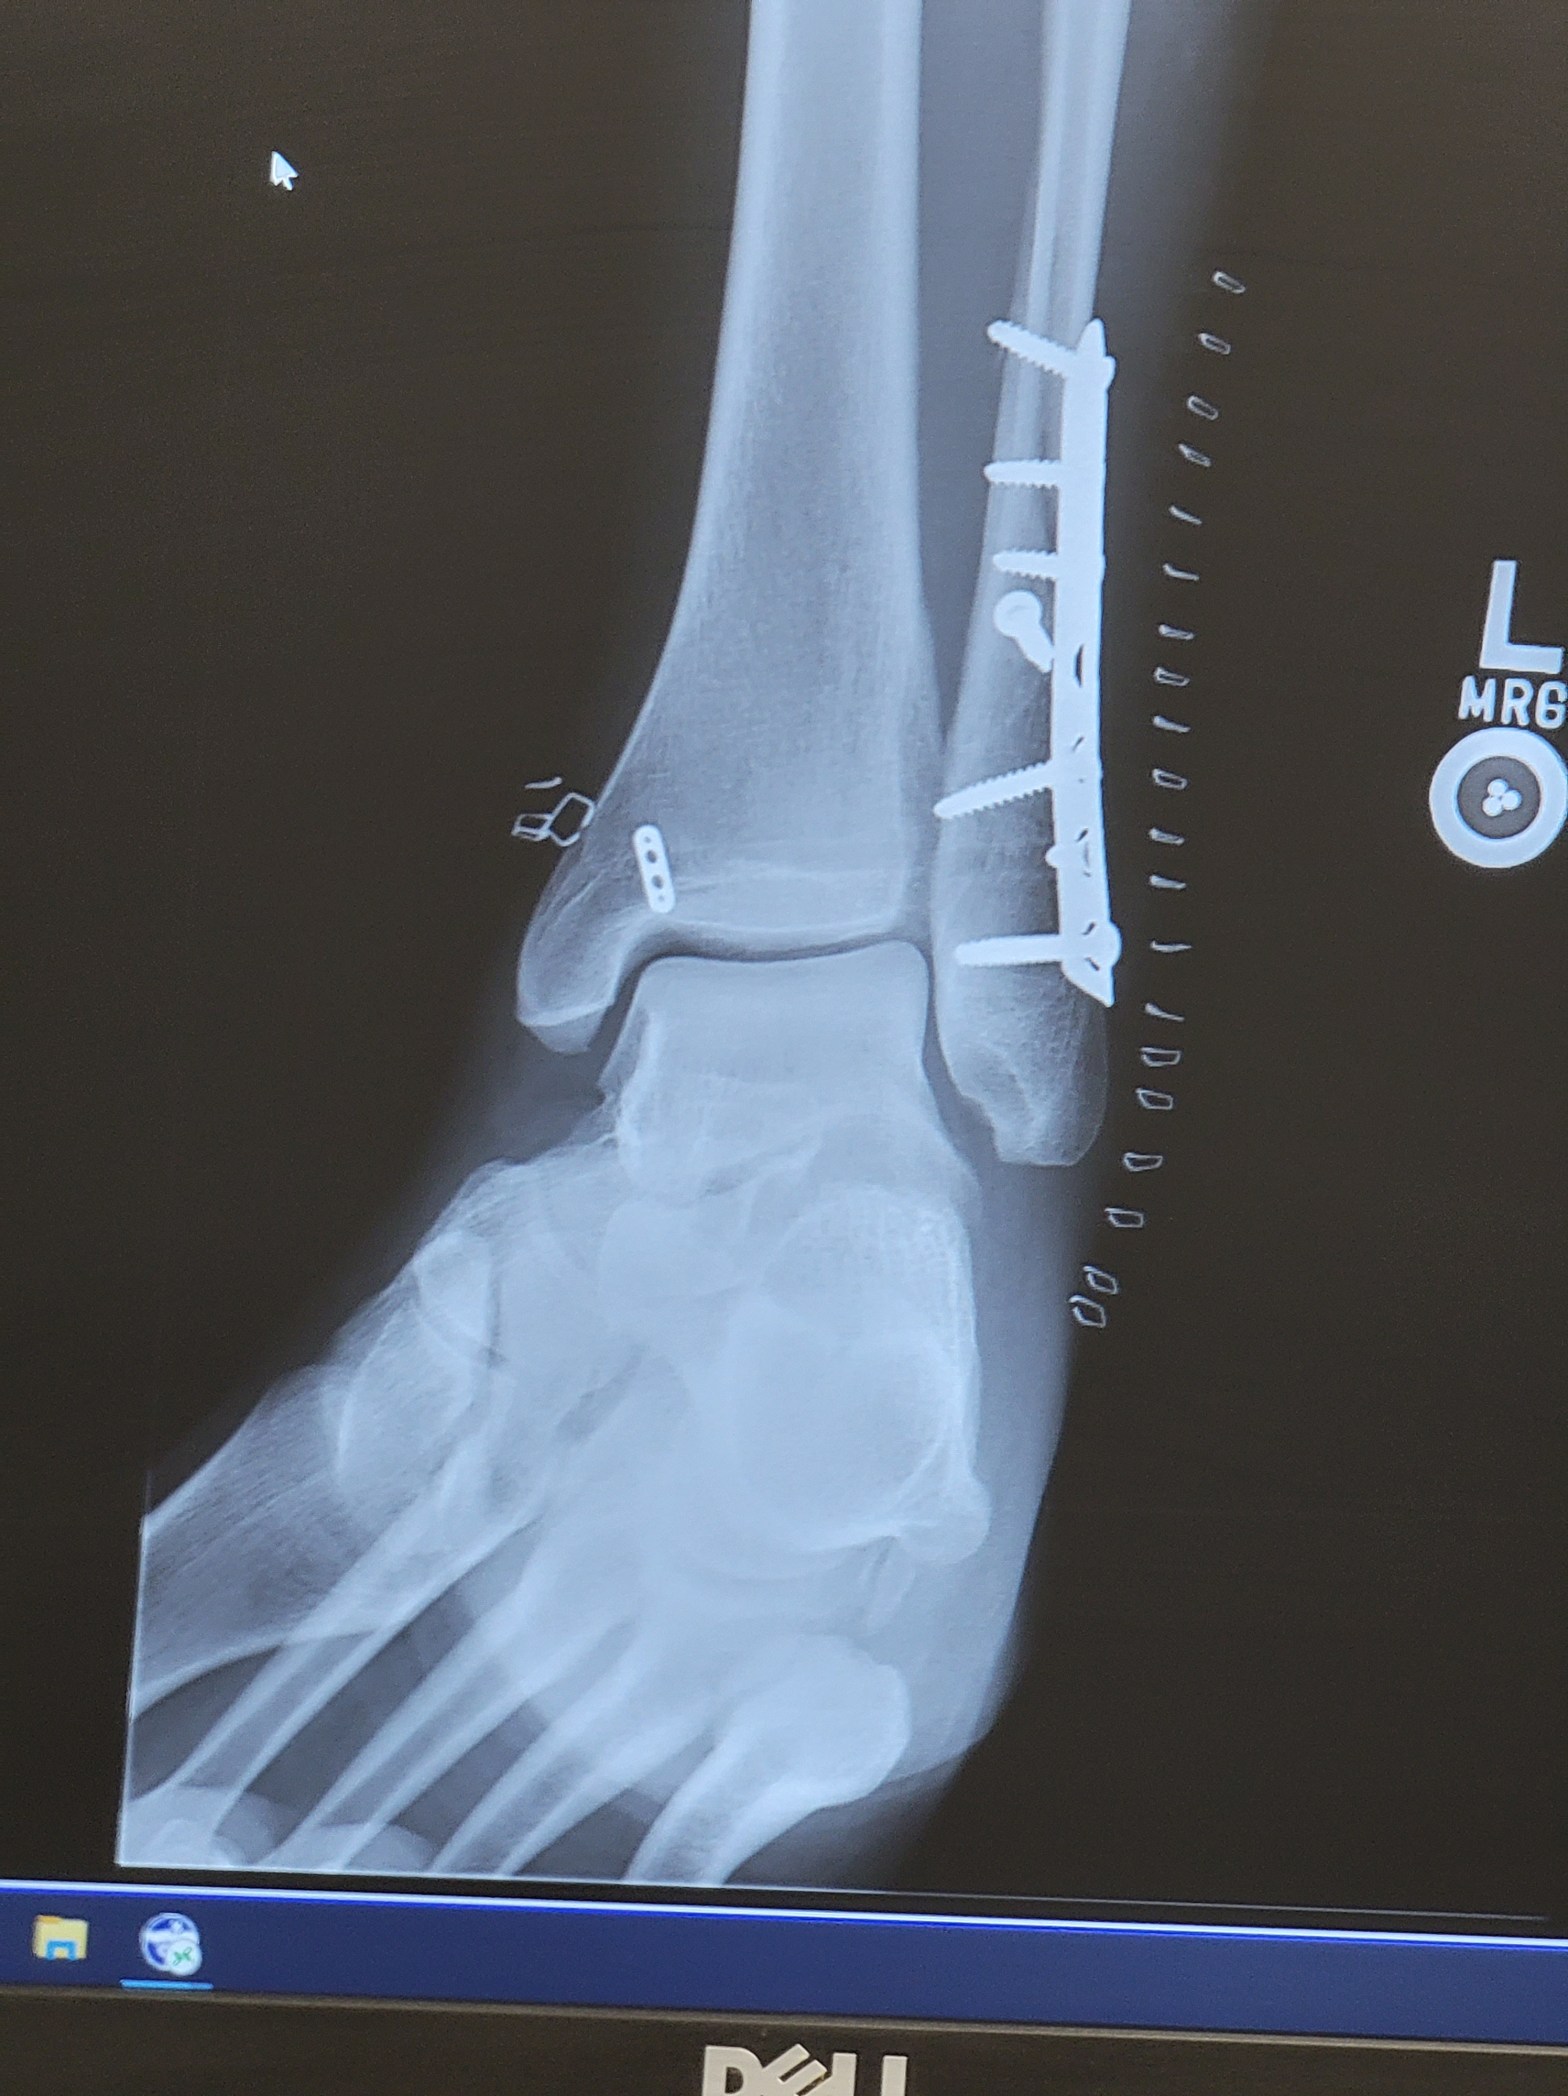

The break was bad enough that it had essentially opened up my ankle joint. If we didn’t fix it properly, I could have long-term issues just walking. A few days later, I was in surgery in Fairbanks, getting everything put back together. Plates, screws, wires… the whole deal.

And all that metal in my ankle now…

That’s my Alaskan souvenir.